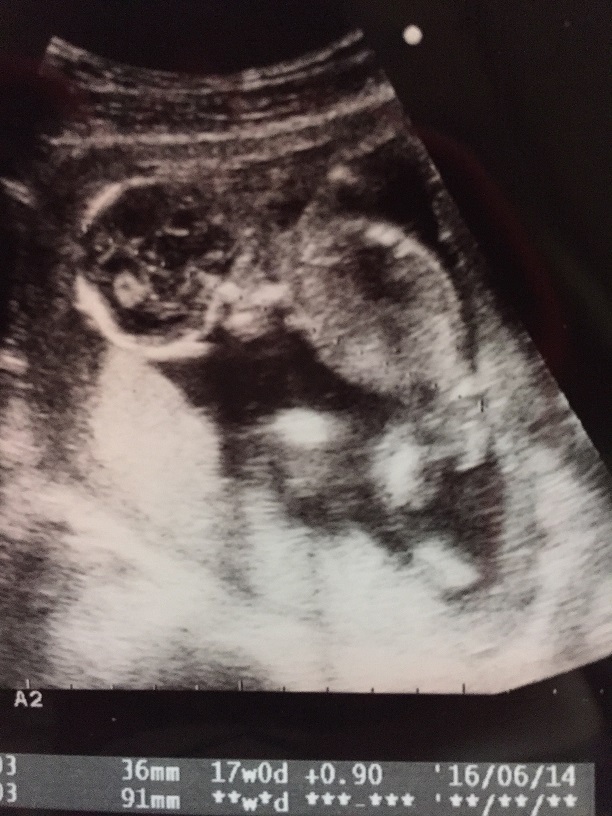

17週1日(17w1d・男の子)|みーぽんぽん さん(28歳)

エコー写真撮影時のエピソード:

初めてちゃんと顔を見せてくれたエコー写真です。顔はこのエコー写真しかなくて、他の写真はいつも手で隠してたので見られませんでした。

そんな中の貴重な顔の写真です!まだ男の子が女の子か分からない時期だったので、毎回診察の時、わくわくしながら見たのを覚えてます。